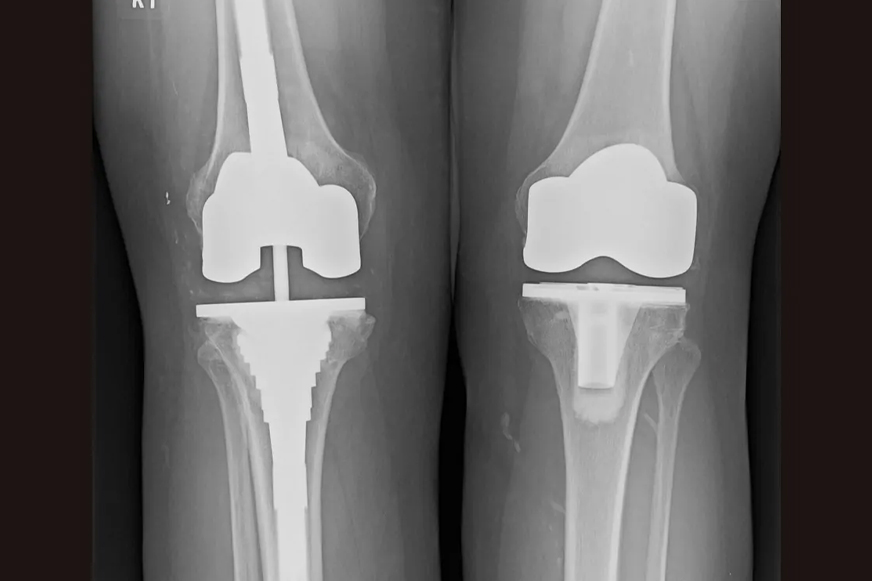

Revision knee replacement is a complex procedure that is carried out to replace one or more components of the previously placed knee implant. Only those parts are removed and replaced that are worn out or damaged. Our specialists are highly experienced to carry out all types of revision surgeries, ranging from single worn or loose components to advanced implant damage involving all the components—femoral, tibial, and patellar.

There are several components of a total knee implant (artificial joint or prosthesis), and each has a specific function:

The following are the techniques used for revision knee replacement, depending on patient needs and type of damage: